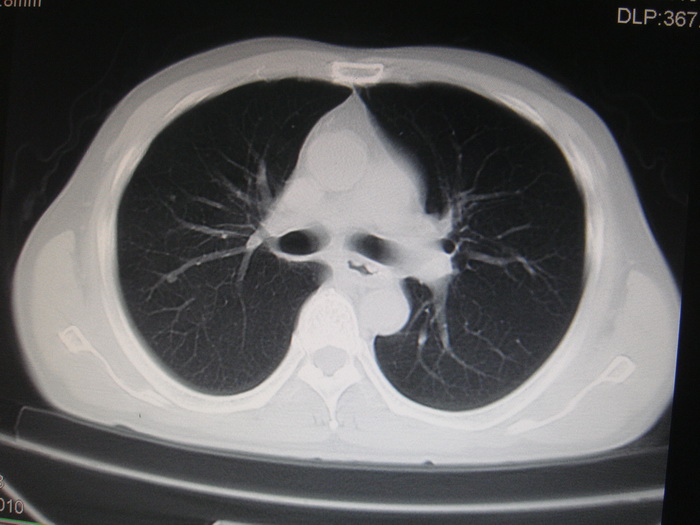

标题: CT28366:男性,45岁,偶尔发现右颈部肿块行胸部CT扫描。 [打印本页]

男性,45岁,偶尔发现右颈部肿块行胸部ct扫描。

两肺多发结节灶及纵膈淋巴结肿大考虑为转移

两肺多发性转移瘤,纵隔淋巴结转移。

两肺多发性转移瘤,纵隔淋巴结转移。食道中上段管壁似乎增厚,作相关检查。

两肺多发性转移瘤,前上纵隔淋巴结转移。